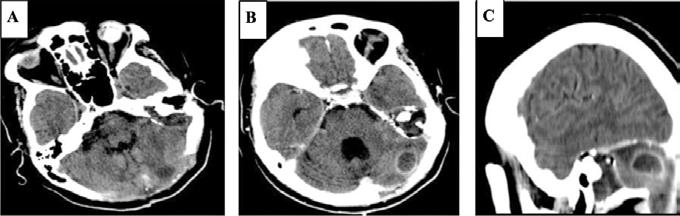

• Studiul opacifierii ramurilor corticale ale arterelor cerebrale medii (M4) drepte și stângi și a venelor cerebrale interne drepte și stângi (Fig.1).

Fig.1 ACTMS cranio-cerebrală, recon MIP în plan axial (a,b) și sagital (c): aspect normal; (a) opacifierea arterelor temporale dreaptă și stângă (săgeţi); (b) opaciferea ramurilor corticale ale arterelor cerebrale medii (M4)-săgeţi albe; opaciferea venelor cerebrale interne dreaptă și stângă (săgeţi negre-b și c).

Semiologie:

▶ Absența opacifierii M4 = 1 punct

▶ Opacifierea M4 = 0 punct

▶ Absența opacifierii venei cerebrale interne = 1 punct

▶ Opacifierea venei cerebrale interne = 0 puncte

• Un scor egal sau mai mare de 3 confirmă stopul circulator intracerebral. In acest caz, concluzia examinării este: „stop circulator intracerebral” care vine în sprijinul diagnosticului clinic de moarte cerebrală sau aspect ACT compatibil cu moartea cerebrală

• În caz contrar, concluzia examinării este „absența opririi circulatiei intracerebrale”, situaţie în care diagnosticul clinic de MC nu este confirmat.

În cazul opacifierii unilaterale a uneia dintre cele două artere cerebrale medii, diagnosticul de MC poate fi afirmată dacă este absentă opacifierea venelor cerebrale interne (Fig,2).